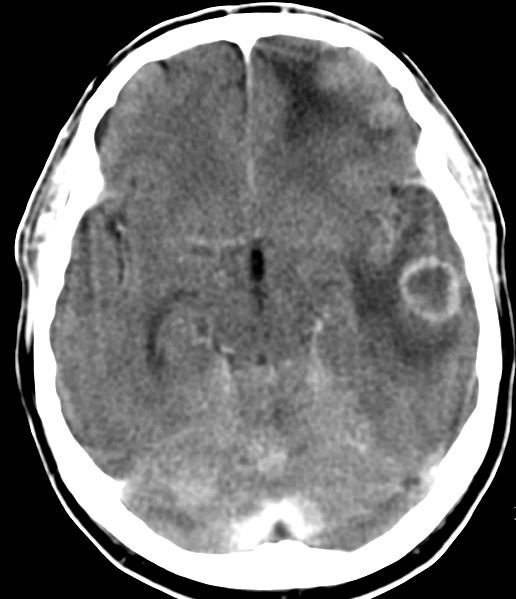

| CT: multiple Hirnmetastasen | Adenokarzinom der Lunge. CT-Untersuchung des Hirns mit Kontrastmittel. | |||

![]() |

![]() | |||